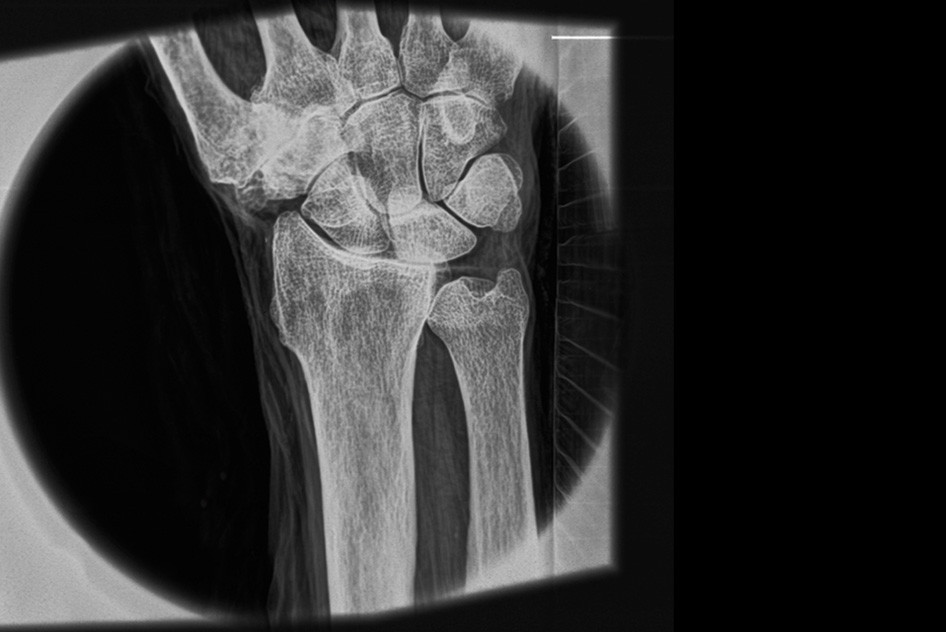

| Снимок запястья, демонстрирующий способность системы «видеть» мягкие ткани. Источник: Luis Velásquez-García et al |

Рентгеновские аппараты не дают возможности получать снимки мягких тканей без контрастных агентов наподобие бария, и разрешение таких снимков невелико. Разработка специалистов Массачусетского технологического института и Массачусетской больницы общего профиля обещает кардинальные перемены: гораздо более детальные снимки, в том числе мягких тканей, без контрастных агентов. К тому же аппарат из МТИ компактнее традиционных и выдает меньшую дозу облучения.

Вместо традиционного одиночного источника большой мощности в новом аппарате используется матрица микроисточников, испускающих когерентный пучок рентгеновских лучей. Такую матрицу исследователи изоготовили, воспользовавшись технологиями, применяемыми в полупроводниковом производстве. По оценкам разработчиков, система позволит получать снимки с разрешением в сотню раз больше, чем обычно, а стоить будет на порядки меньше, чем традиционные аппараты.